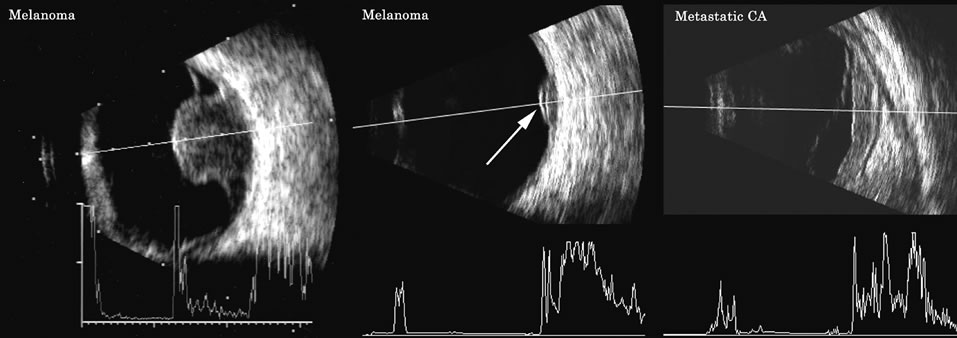

the monitoring of therapy. Trans Am Ophthalmol Soc 85:49, 1987 28. Ossoinig KC: Standardized echography: Basic principles, clinical applications, and results. Int Ophthalmol Clin 19:127, 1979 29. Ursea R, Coleman DJ, Silverman RH, et al: Correlation of high-frequency ultrasound backscatter with tumor

microstructure in iris melanoma. Ophthalmol 105:906, 1998 30. Feleppa EJ, Lizzi FL, Coleman DJ, et al: Diagnostic spectrum analysis in ophthalmology: A physical perspective. Ultrasound Med Biol 12:623, 1986 31. Coleman DJ, Lizzi FL: Computer-processed acoustic spectral analysis of ophthalmic tissues. Trans Am Acad Ophthalmol Otolaryngol 83: 725, 1977 32. Coleman DJ, Lizzi FL: Computerized ultrasonic tissue characterization of ocular tissues. Am J Ophthalmol 96:165, 1983 33. Green RL, Byrne SF: Diagnostic ophthalmic ultrasound. In Ryan SJ (ed): Retina, pp 191–273. Vol 1. St. Louis, CV Mosby, 1989 34. Shammas HJ: Atlas of Ophthalmic Ultrasonography and Biometry, p 68. St. Louis, CV Mosby, 1984 35. Nicholson DH, Frazier-Byrne S, Chiu MT: Echographic and histologic tumor height measurements in uveal melanoma. Am J Ophthalmol 100:454, 1985 36. Coleman DJ, Abramson DH, Jack RL, et al: Ultrasonic diagnosis of tumors of the choroid. Arch Ophthalmol 91:344, 1974 37. Cusumano A, Coleman DJ, Silverman RH, et al: Three-dimensional ultrasound imaging. Clinical applications. Ophthalmology 105:300, 1998 38. Lee W, Kirk J, Comstock C, Romero R: Vasa previa: Prenatal detection by three-dimensional ultrasonography. Ultrasound Obstet Gynecol 16:384, 2000 39. Lee W, Kirk J, Shaheen K, et al: Fetal cleft lip and palate detection by three-dimensional ultrasonography. Ultrasound Obstet Gynecol 16:314, 2000 40. Lee W, McNie B, Chaiworapongsa T, et al: Three-dimensional ultrasonographic presentation of micrognathia. J Ultrasound Med 21:775, 2002 41. Fisher Y, Hanutsaha P, Tong S, et al: Three-dimensional ophthalmic contact B-scan ultrasonography

features as a predictor of death. Am J Ophthalmol 110:380, 1990 48. Silverman RH, Folberg R, Boldt HC, et al: Correlation of ultrasound parameter imaging with microcirculatory patterns

in uveal melanomas. Ultrasound Med Biol 23:573, 1997 |